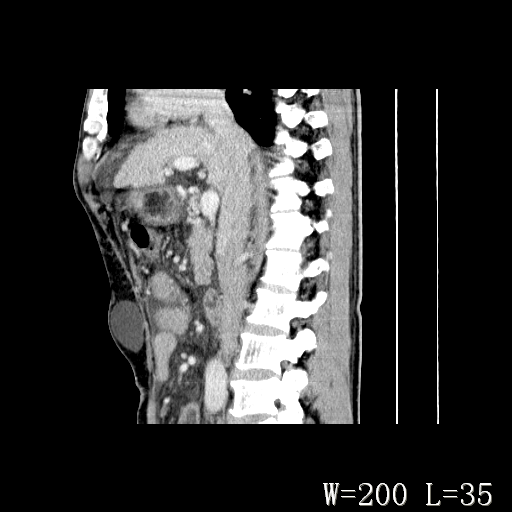

男,52岁,门脉高压断流术后1年,发现腹部肿物2月。

1)前腹壁中线区(脐上方)囊性占位性病变,考虑淋巴囊肿。2)腹水。